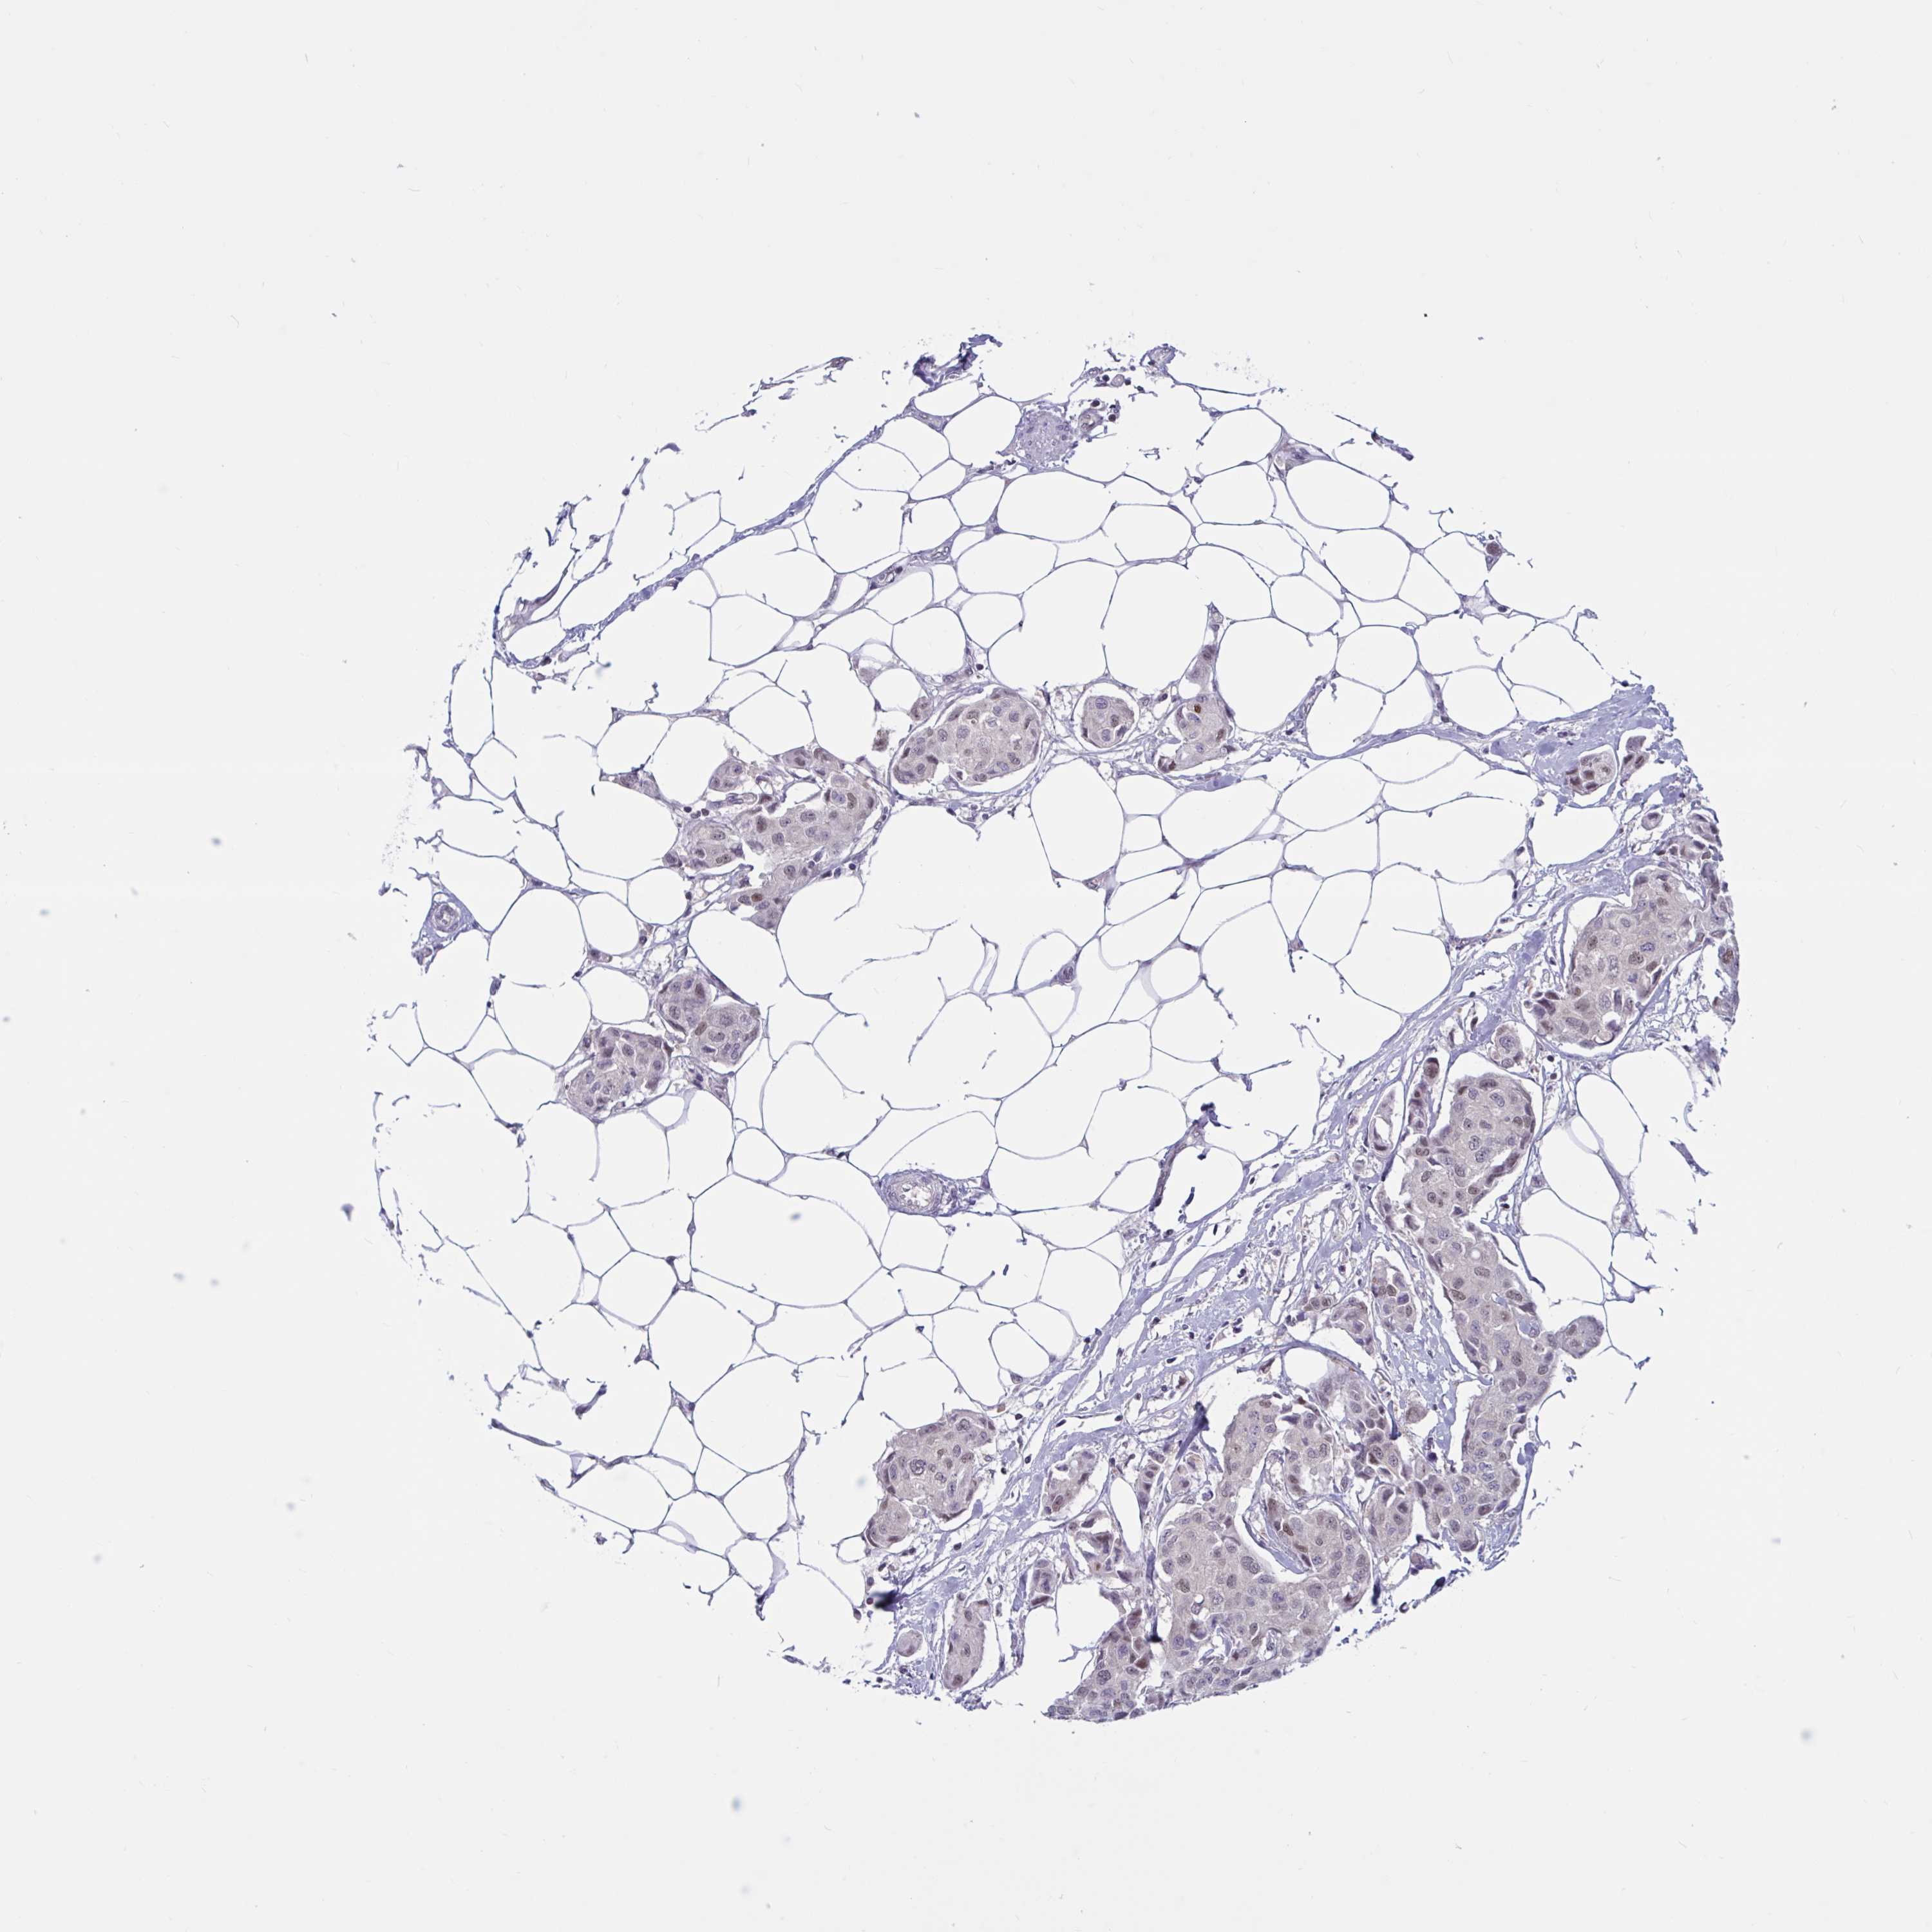

CANCER BREAST CANCER Show tissue menu

BRCA TCGA BRCA VALIDATION PROTEIN EXPRESSION

Breast cancer

Human cancer

Breast invasive carcinoma